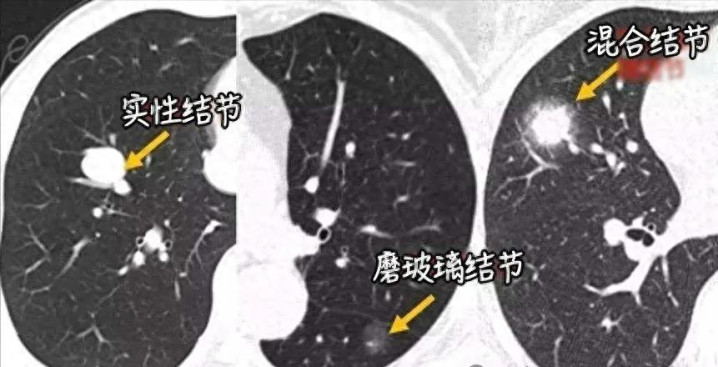

关于肺结节患者来说,最状貌的可能即是结节的良恶性。通过CT影像,频繁咱们会把肺结节分为三大类:实性结节、纯磨玻璃结节、混杂磨玻璃结节,它们的恶性风险高下确有不同:

实性结节:密度最高,如归拢个小棉球,相对来说风险进度是最低的,指南中也提到,若是随访跨越2年莫得变化,则基本上判定为良性;不外需要进展的是,天然实性结节的恶性风险最低,但并不虞味着就一定是安全的,其一朝确诊为恶性的,连接恶性进度齐比拟高;

纯磨玻璃结节:像一派薄雾,密度较低,风险进度居中,即使是恶性的,发展也极其慢慢,且恶性进度较低;

混杂磨玻璃结节:如同薄雾中藏着一个更密实的中枢。参谋标明,这类结节的恶性概率最高,关通盘据清楚以致可达60%以上,尤其当其中的实性因素增多时,风险显贵加多。天然,风险高不等于一定是癌。中医合计,混杂磨玻璃结节的中枢病机常是"浩气不及,痰瘀互结",这恰是咱们散结的重心。